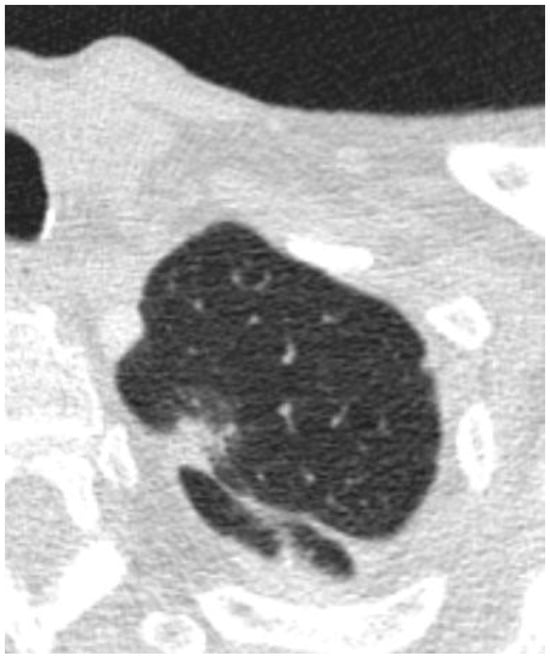

Figure 3.

(a–c) Axial images depicting nodules that were found to be invasive on resection.